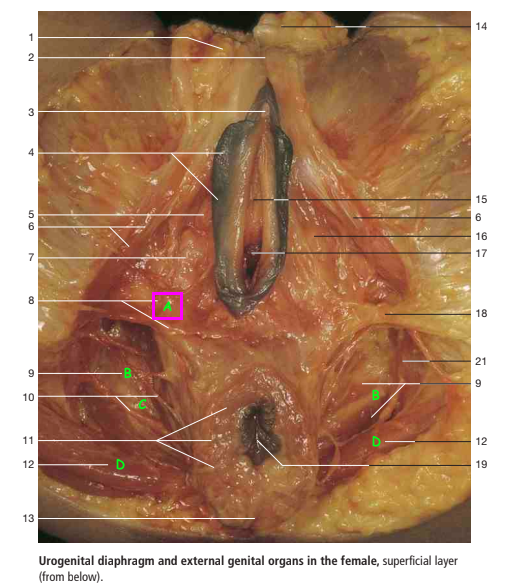

Label A-E of female anatomy [5]

A

A: bulb of the vestibule

B: levator ani

C: Obturator internus muscle

D: Left ureteric orifice

E: Muscular coat of urinary bladder